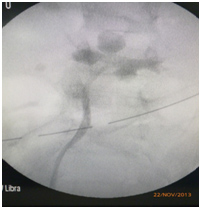

| Retrograde pyelogram | Robotic pyeloplasty | |

| Preoperative Retrograde pyelogram | Postoperative pyelogram | |